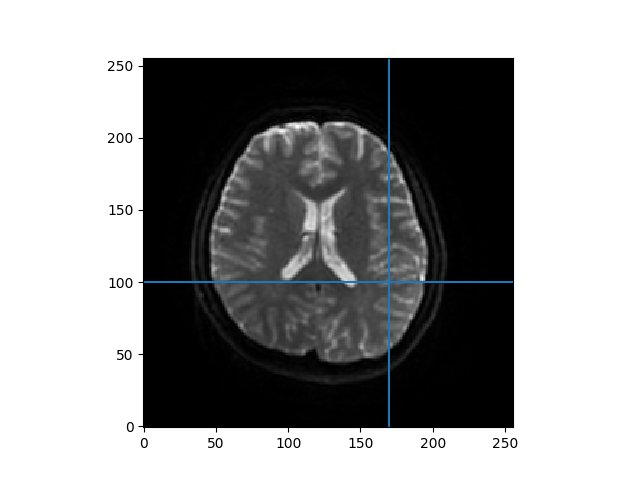

The data has 54 slices, with 256-by-256 voxels in each slice. The fourth dimension corresponds to the b-values in the gtab. Let us visualize the data by taking a slice midway(z=33) at \(\mathbf{b} = 0\).

Heat map of a slice of data

The region around the intersection of the cross-hairs in the figure contains cerebral spinal fluid (CSF), so it should have a very high \(\mathbf{f}\) and \(\mathbf{D^*}\), the area just medial to that is white matter so that should be lower, and the region more laterally contains a mixture of gray matter and CSF. That should give us some contrast to see the values varying across the regions.